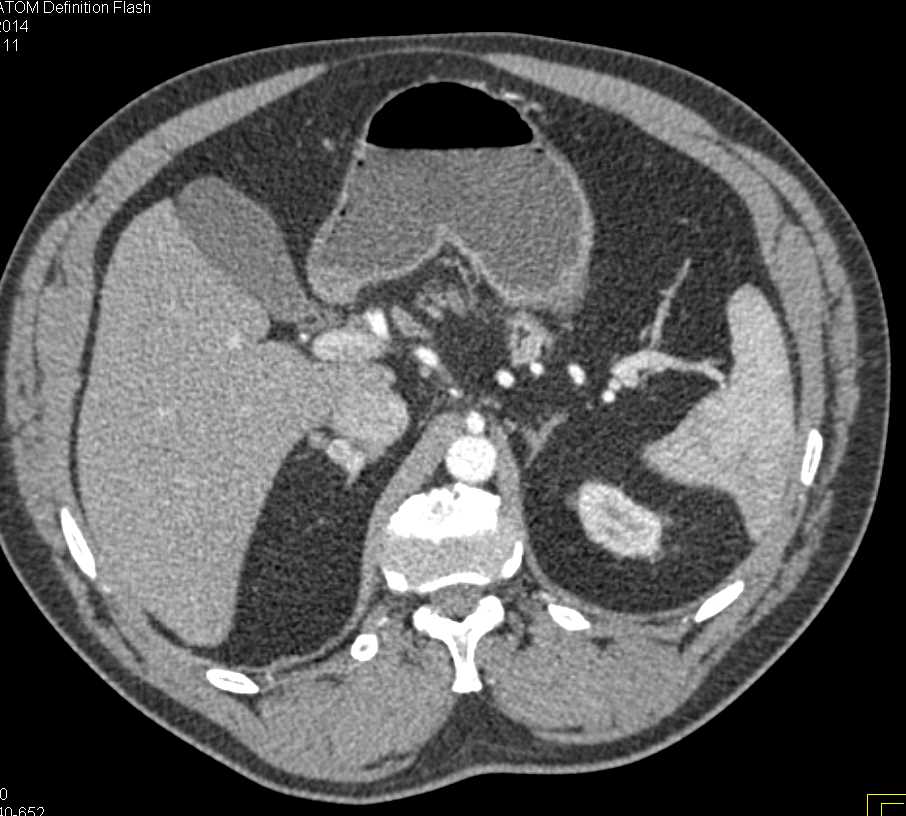

Enhancing Adrenal Glands in a Hypotensive Patient who Incidentally had Superior Mesenteric Artery (SMA) Syndrome